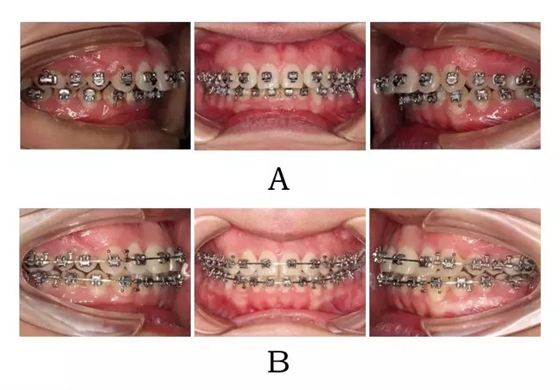

640.webp (2).jpg

圖4-2:混合I型突面畸形SGTB矯形及后期常規(guī)固定矯治。

(A)SGTB矯形 (B)后期固定矯治

Figure 4-2. SGTB therapy for merged prognathism (Type I). (A) SGTB orthopedics at early stage.(B) Fixed orthodontics at late stage.